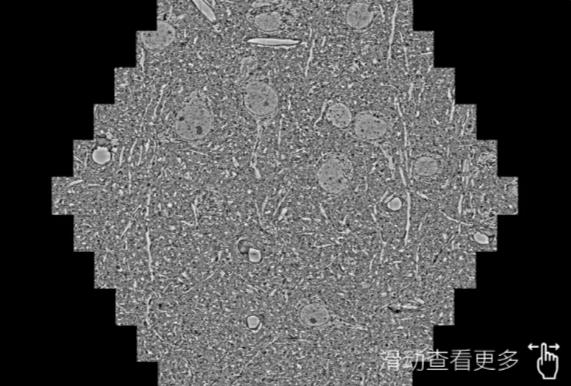

鼠脑切片。左图使用津南蔡司津南扫描电镜MultiSEM706对165μmx143pm面积区域成像,耗时仅需1.5秒。右图为鼠脑切片中30μm区域放大效果。样品由芝加哥大学B.Kasthuri提供。

使用蔡司高速津南扫描电镜MultiSEM对1mm²人脑皮层组织进行高分辨成像,并对其中的各种细胞结构进行三维重构分析。左图展示了2x3mm²组织平面中锥体神经元的三维重构效果。右图显示了局部体积神经元三维重构。图像由哈佛大学chtman实验室提供,渲染图由D. Berger 制作。